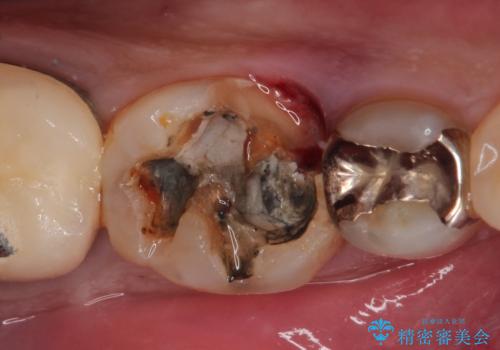

- 「硬い物を食べたら歯が割れた」を主訴に来院された患者さんです。

根っこのところまで歯が割れていたため、歯を残すことは不可能と診断し抜歯後、インプラントで治療を行いました。

破折の深さが歯根まで及んでいたため抜歯を行いました。